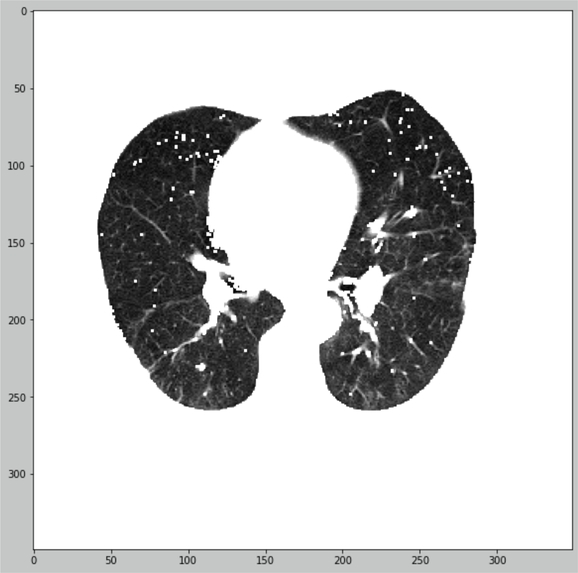

We offer the principle of lungs CT-images quantification with segmentation preprocessing

- Mask applied and lungs tissue HU-values calculated

- Magic here!

- COVID-19/Interstitial/Norma classifier